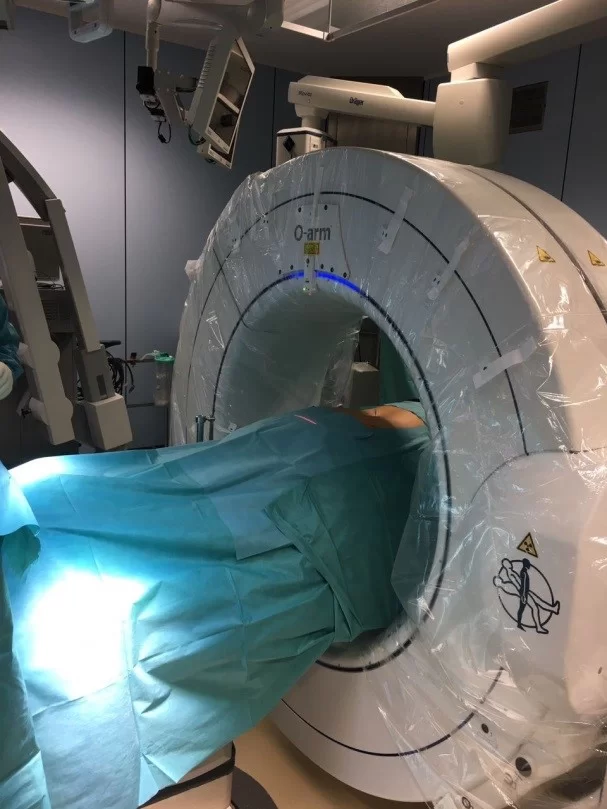

Σημαντική βοήθεια για τη διενέργεια τέτοιων επεμβάσεων αποτελεί η τρισδιάστατη νευροπλοήγηση της σπονδυλικής στήλης, η οποία επιτρέπει τα υλικά να τοποθετούνται με ακρίβεια χιλιοστού (Εικόνα 1 και 2).